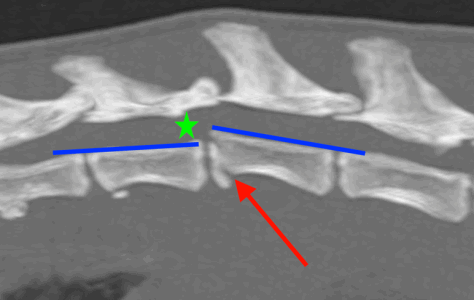

Osiris was assessed by our anaesthesia team and nurses who stabilised him so that he could be anaesthetised. Under a general anaesthetic, a CT of the back confirmed the fracture in his spine (red arrow on images below). The vertebral canal (green star) is where the spinal cord runs. The floor of the vertebral canal (blue lines) should be level and as you can see in the images there is a step in the floor, resulting in pressure on the spinal cord. The image on the right also shows a deviation in the spine (the purple lines should be straight), also adding pressure to the spinal cord. This pressure means that the neurotransmission pathway between the brain and legs is disrupted, which ultimately meant that Osiris couldn’t use his hindlimbs.